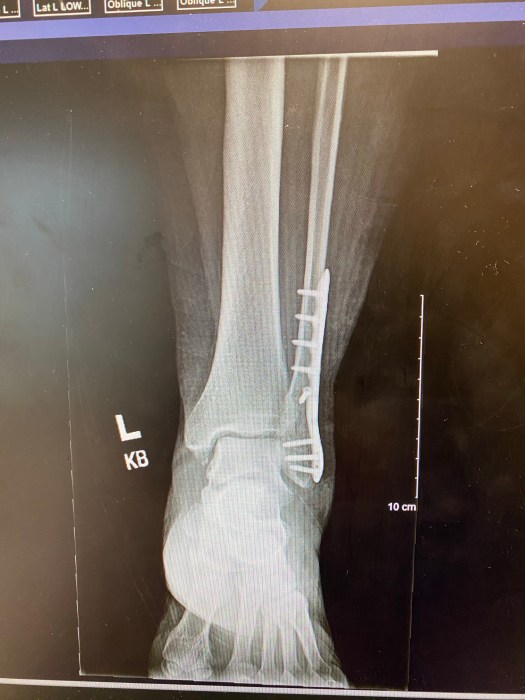

After 2 weeks we went in to see the Physician’s Assistant who works with the surgeon. I got to see the fancy new hardware.